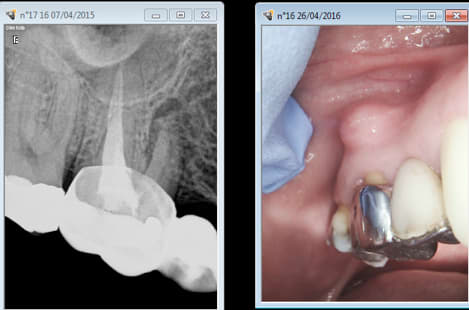

26/04/2016 à 14h31

Je ne comprends pas, pourtant j'avais tout mis en oeuvre pour faire cette superbe endo tarif sécu de merde ! -)

Capture d e cran 2016 04 26 12.30 - Eugenol